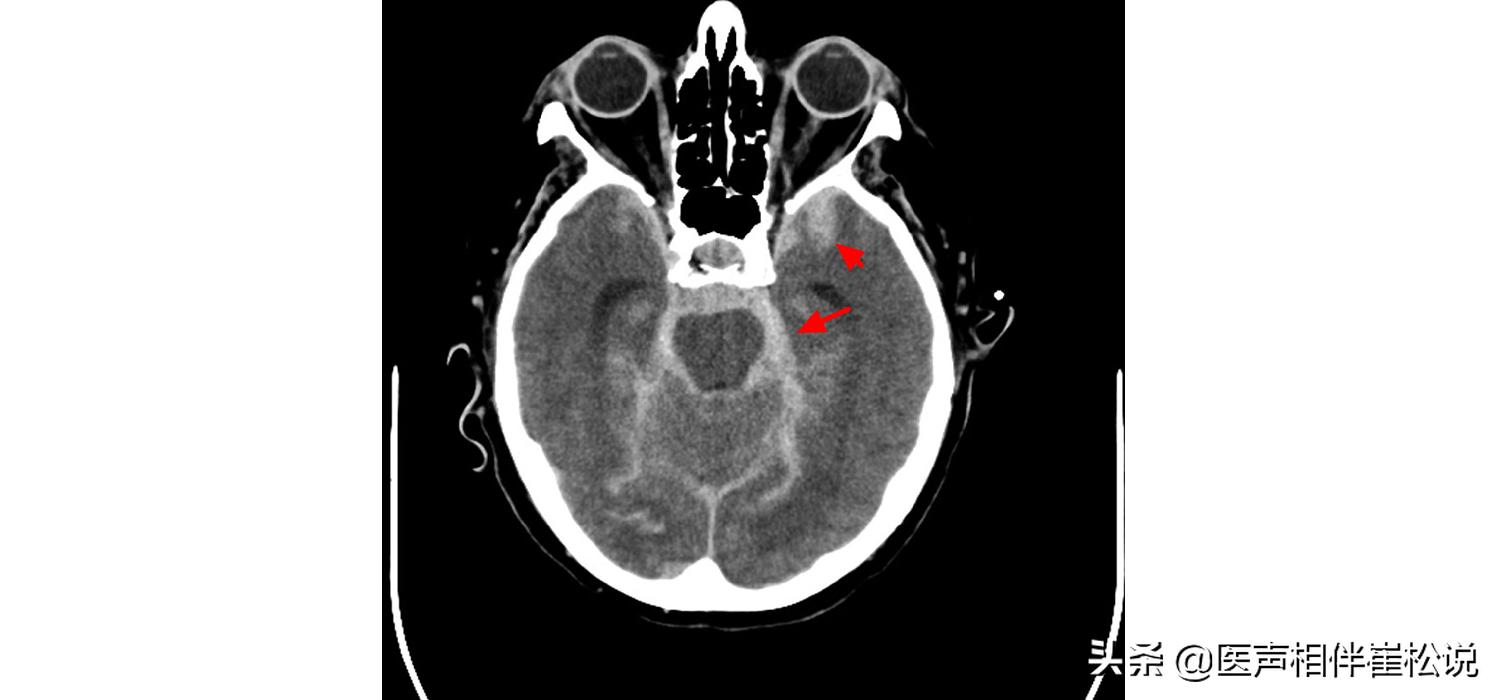

如果一旦怀疑是脑出血,就要做一个脑部CT,看一下脑出血 发生的部位和出血量。

蛛网膜下腔出血

除了脑出血之外,还有一种疾病也是脑血管破裂,但它不是破在大脑里面的动脉,而是破在脑子外面包的一层滋养血管,叫“蛛网膜下腔出血”。

▲但是蛛网膜下腔出血的“破”不是破在脑子当中,而是破在外面,也就是说整个脑子浸在了血液当中,这会引起 强烈的脑血管痉挛 。